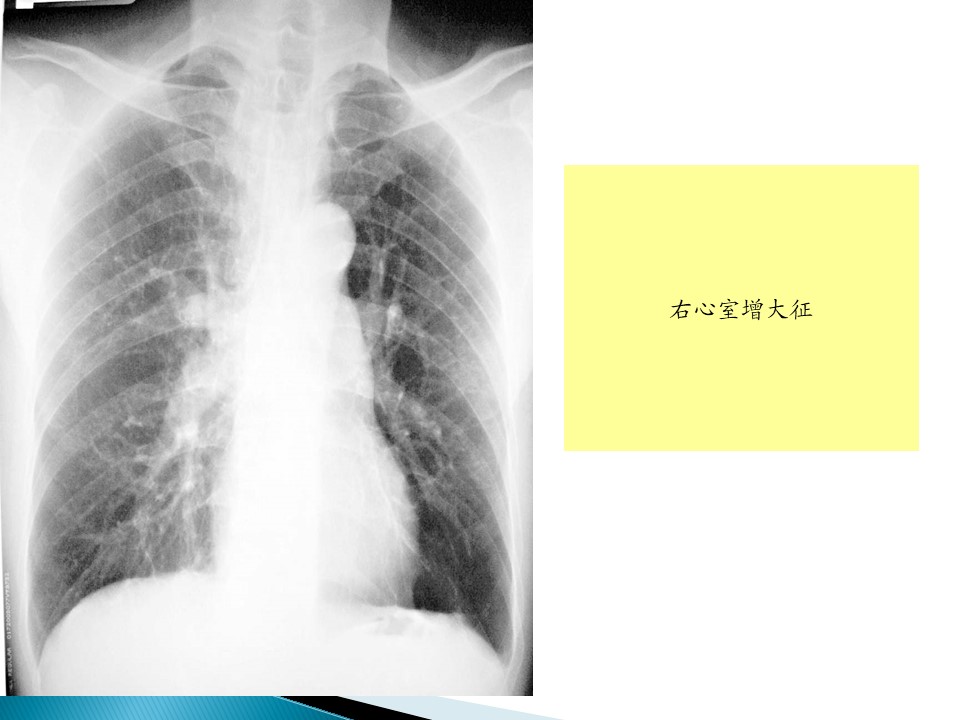

• 3.3 肺心病

肺心病